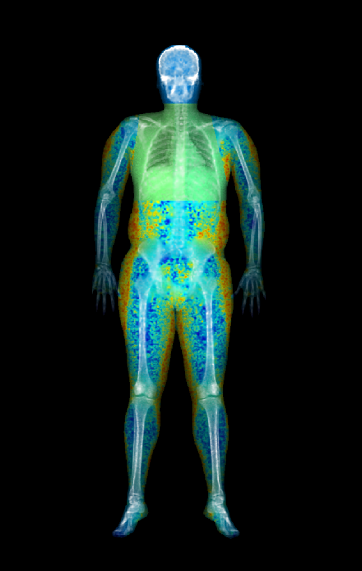

Body composition analysis

Our DXA machine goes further using a large scan area for complete analysis of the whole body by separating tissues across body regions. The device offers detailed body composition measurements:

– Fat and lean tissue color mapping, Android/Gynoid ratios

– Metabolic indicators like Visceral Adipose Tissue (VAT)

– Sarcopenia assessment tool